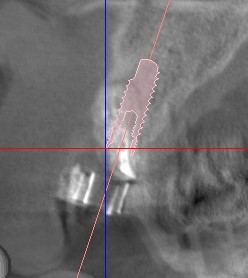

その前にインプラントのシュミレーションをしますと

十分な骨がありますので抜歯即時埋入を計画しました。